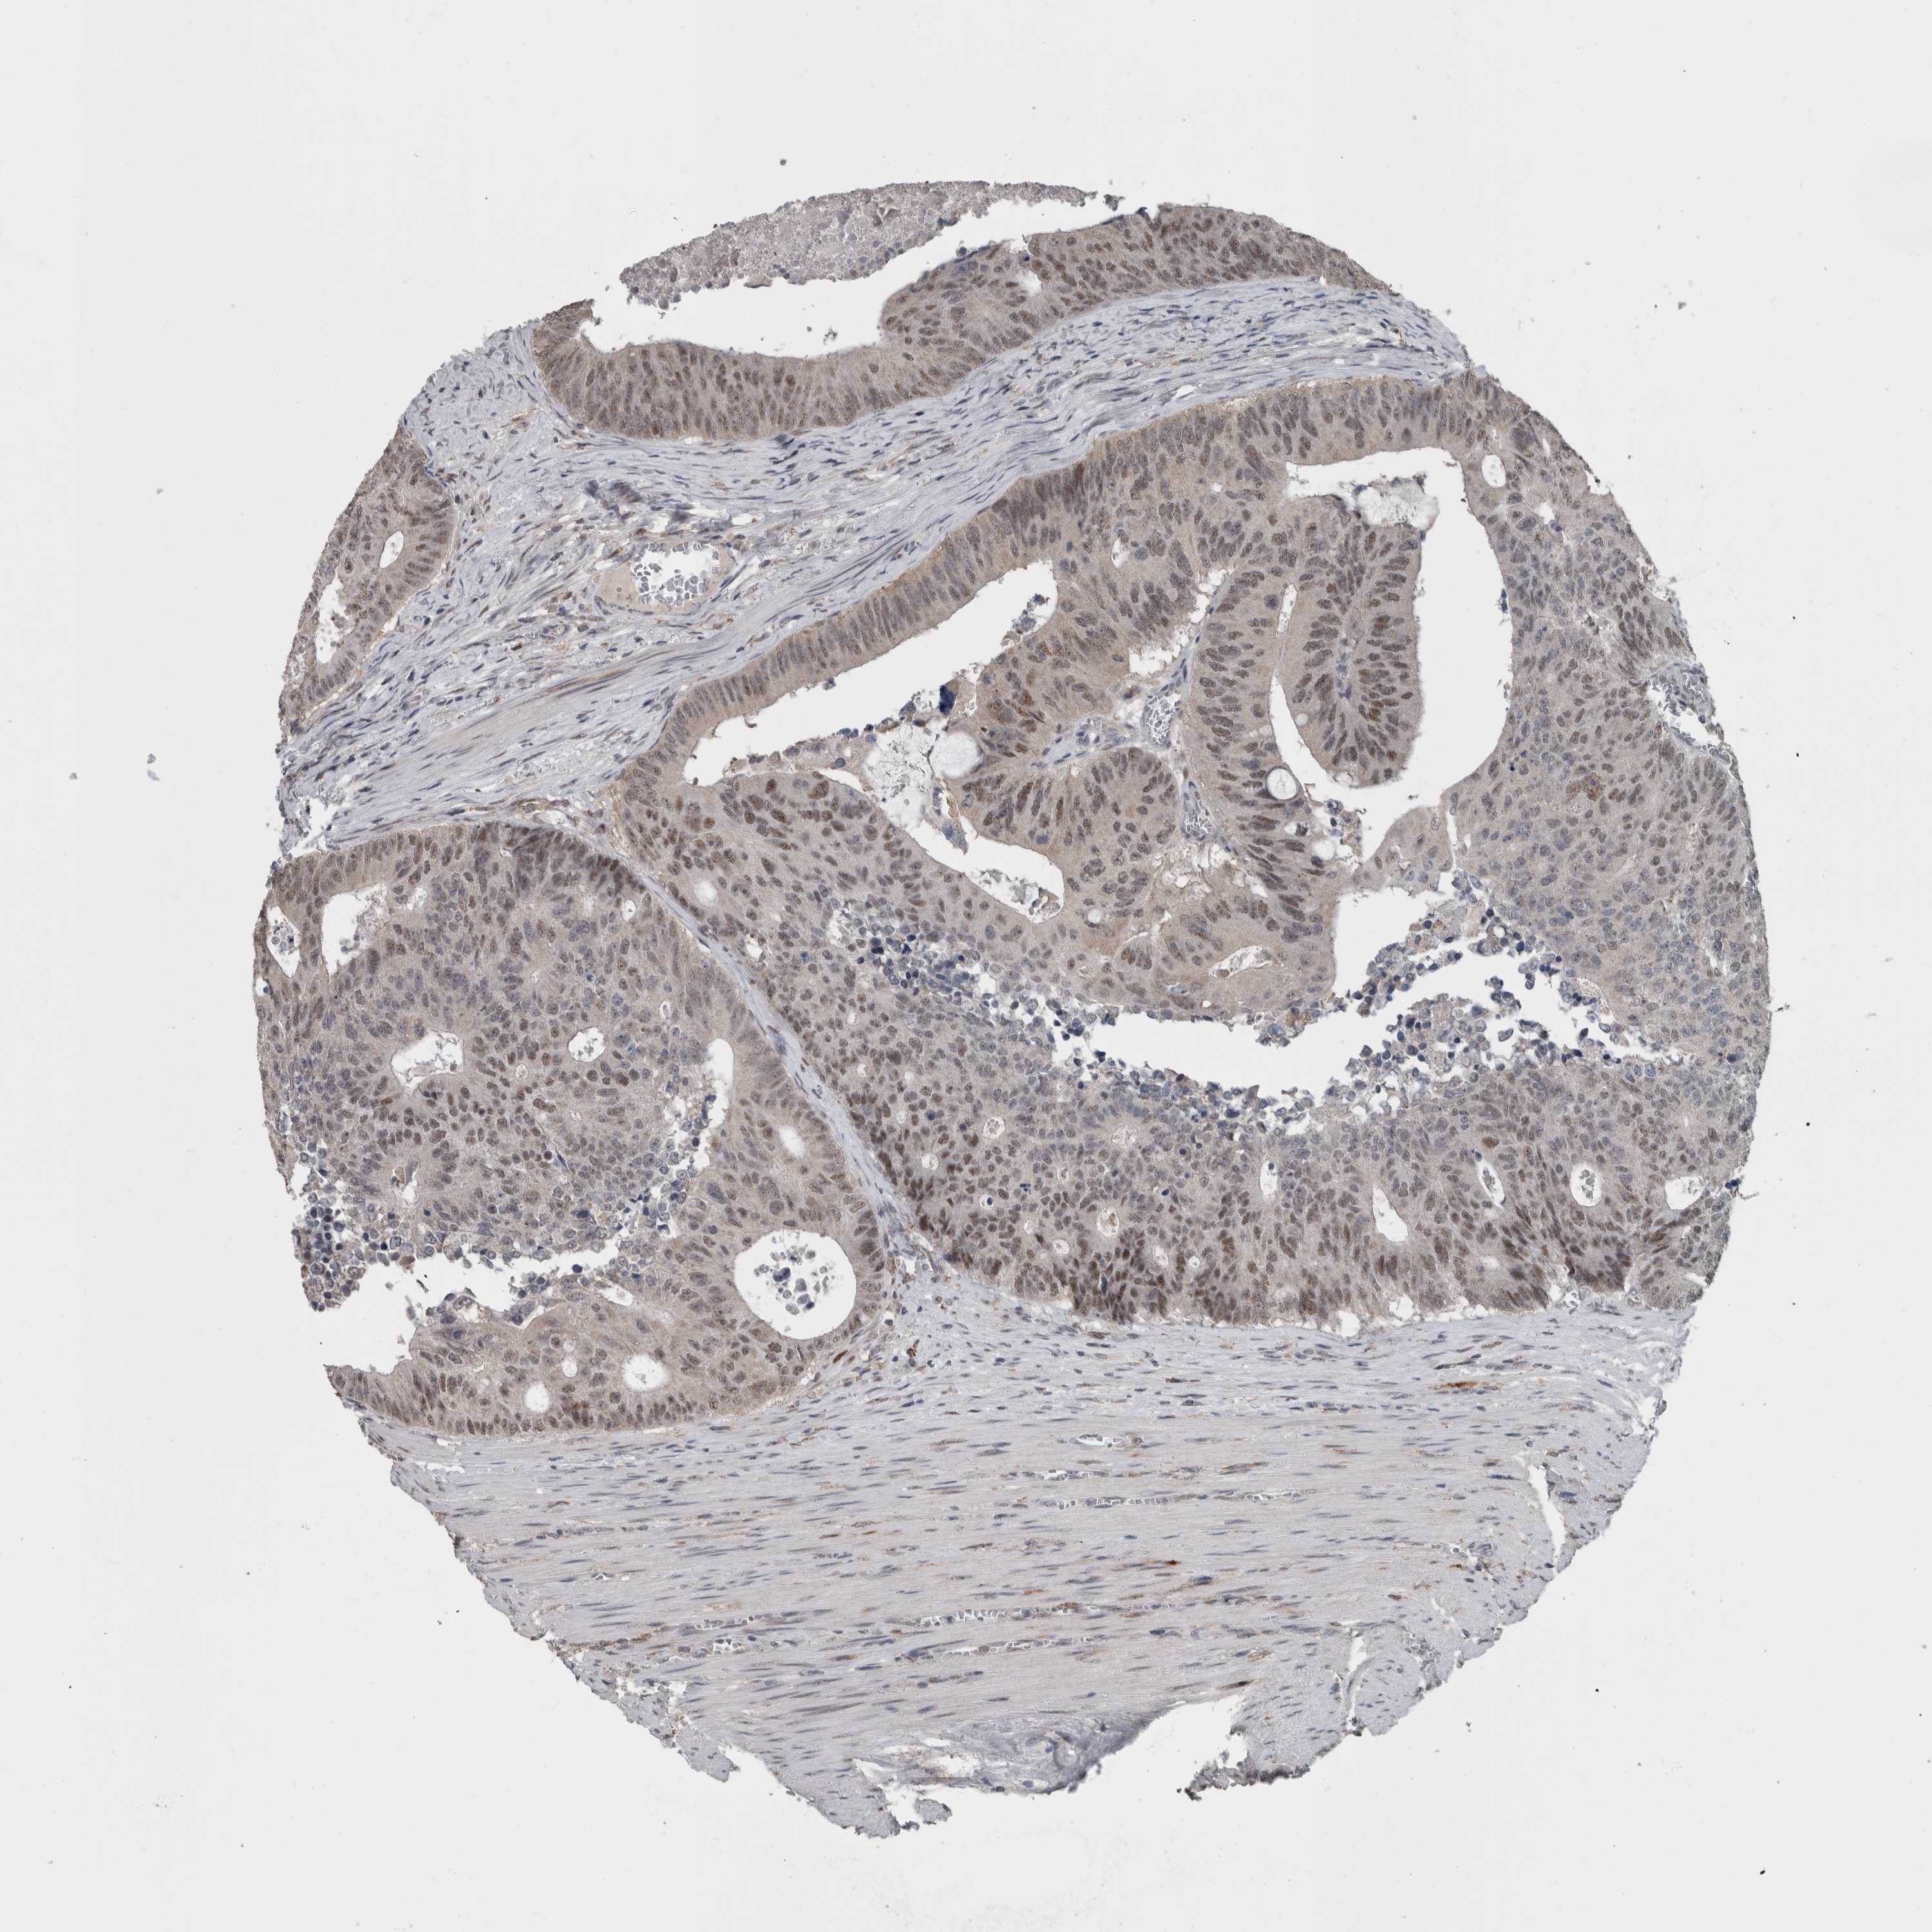

CANCER COLORECTAL CANCER Show tissue menu

Colorectal cancer

Colon adenocarcinoma